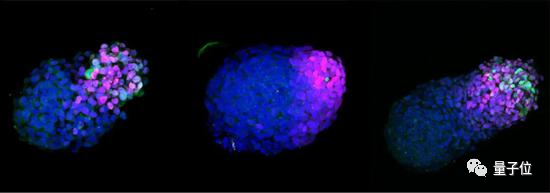

结果发现,有将近60%的细胞都在进行「原肠胚形成」过程,形成了3D「类原肠胚」结构,细胞分化形成三胚层的衍生物中,类原肠胚拉长,产生前后端。

△培养24小时、48小时和72小时的人类类原肠胚,蓝色标记为DNA,红色为神经细胞,绿色为中胚层细胞

不过这个「类原肠胚」最终只存活了4天就自行崩溃了。

通过观察关键的基因表达变化,发现这个只有3天年纪的类原肠胚可以模拟出21天大的人类胚胎的一些关键特征。

这就是他们制作出来的3天大的类原肠胚,已经有了明显的「前后端」,可以模拟出大概21天大的人类胚胎的一些关键特征。